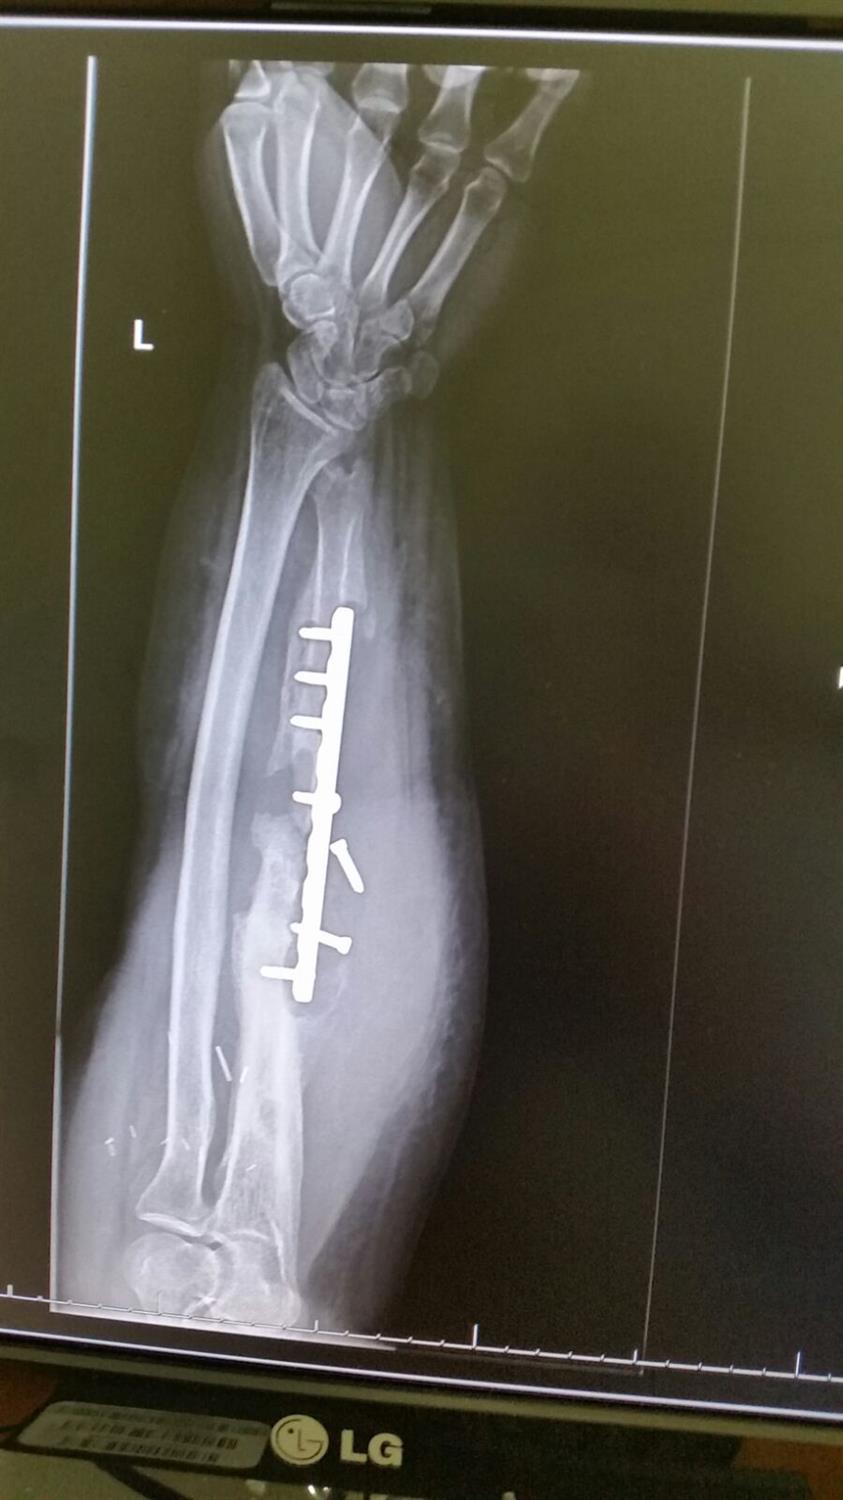

Radius and Ulnar Shaft Fractures Trauma Orthobullets Radius Ulna Fracture Orthobullets The ulnar styloid plays a crucial role in the. — distal radius fractures are the most common orthopaedic injury and generally result from fall on an outstretched hand. — ulnar styloid fracture occurs together with distal radius fracture that has high degree of initial displacement. — evaluate druj and elbow for associated injuries (galezzi, monteggia fractures) check. Radius Ulna Fracture Orthobullets.

Radius and Ulnar Shaft Fractures Trauma Orthobullets Radius Ulna Fracture Orthobullets ulnar styloid fracture is commonly associated with distal radius fracture (drf). — distal radius fractures are the most common orthopaedic injury and generally result from fall on an outstretched hand. — ulnar styloid fracture occurs together with distal radius fracture that has high degree of initial displacement. — evaluate druj and elbow for associated injuries (galezzi,. Radius Ulna Fracture Orthobullets.

Radius and Ulnar Shaft Fractures Trauma Orthobullets Radius Ulna Fracture Orthobullets — evaluate druj and elbow for associated injuries (galezzi, monteggia fractures) check compartment pressure. distal radius fractures are the most common upper extremity fracture and account for over a sixth of all fractures seen in emergency. — ulnar styloid fracture occurs together with distal radius fracture that has high degree of initial displacement. The ulnar styloid plays. Radius Ulna Fracture Orthobullets.